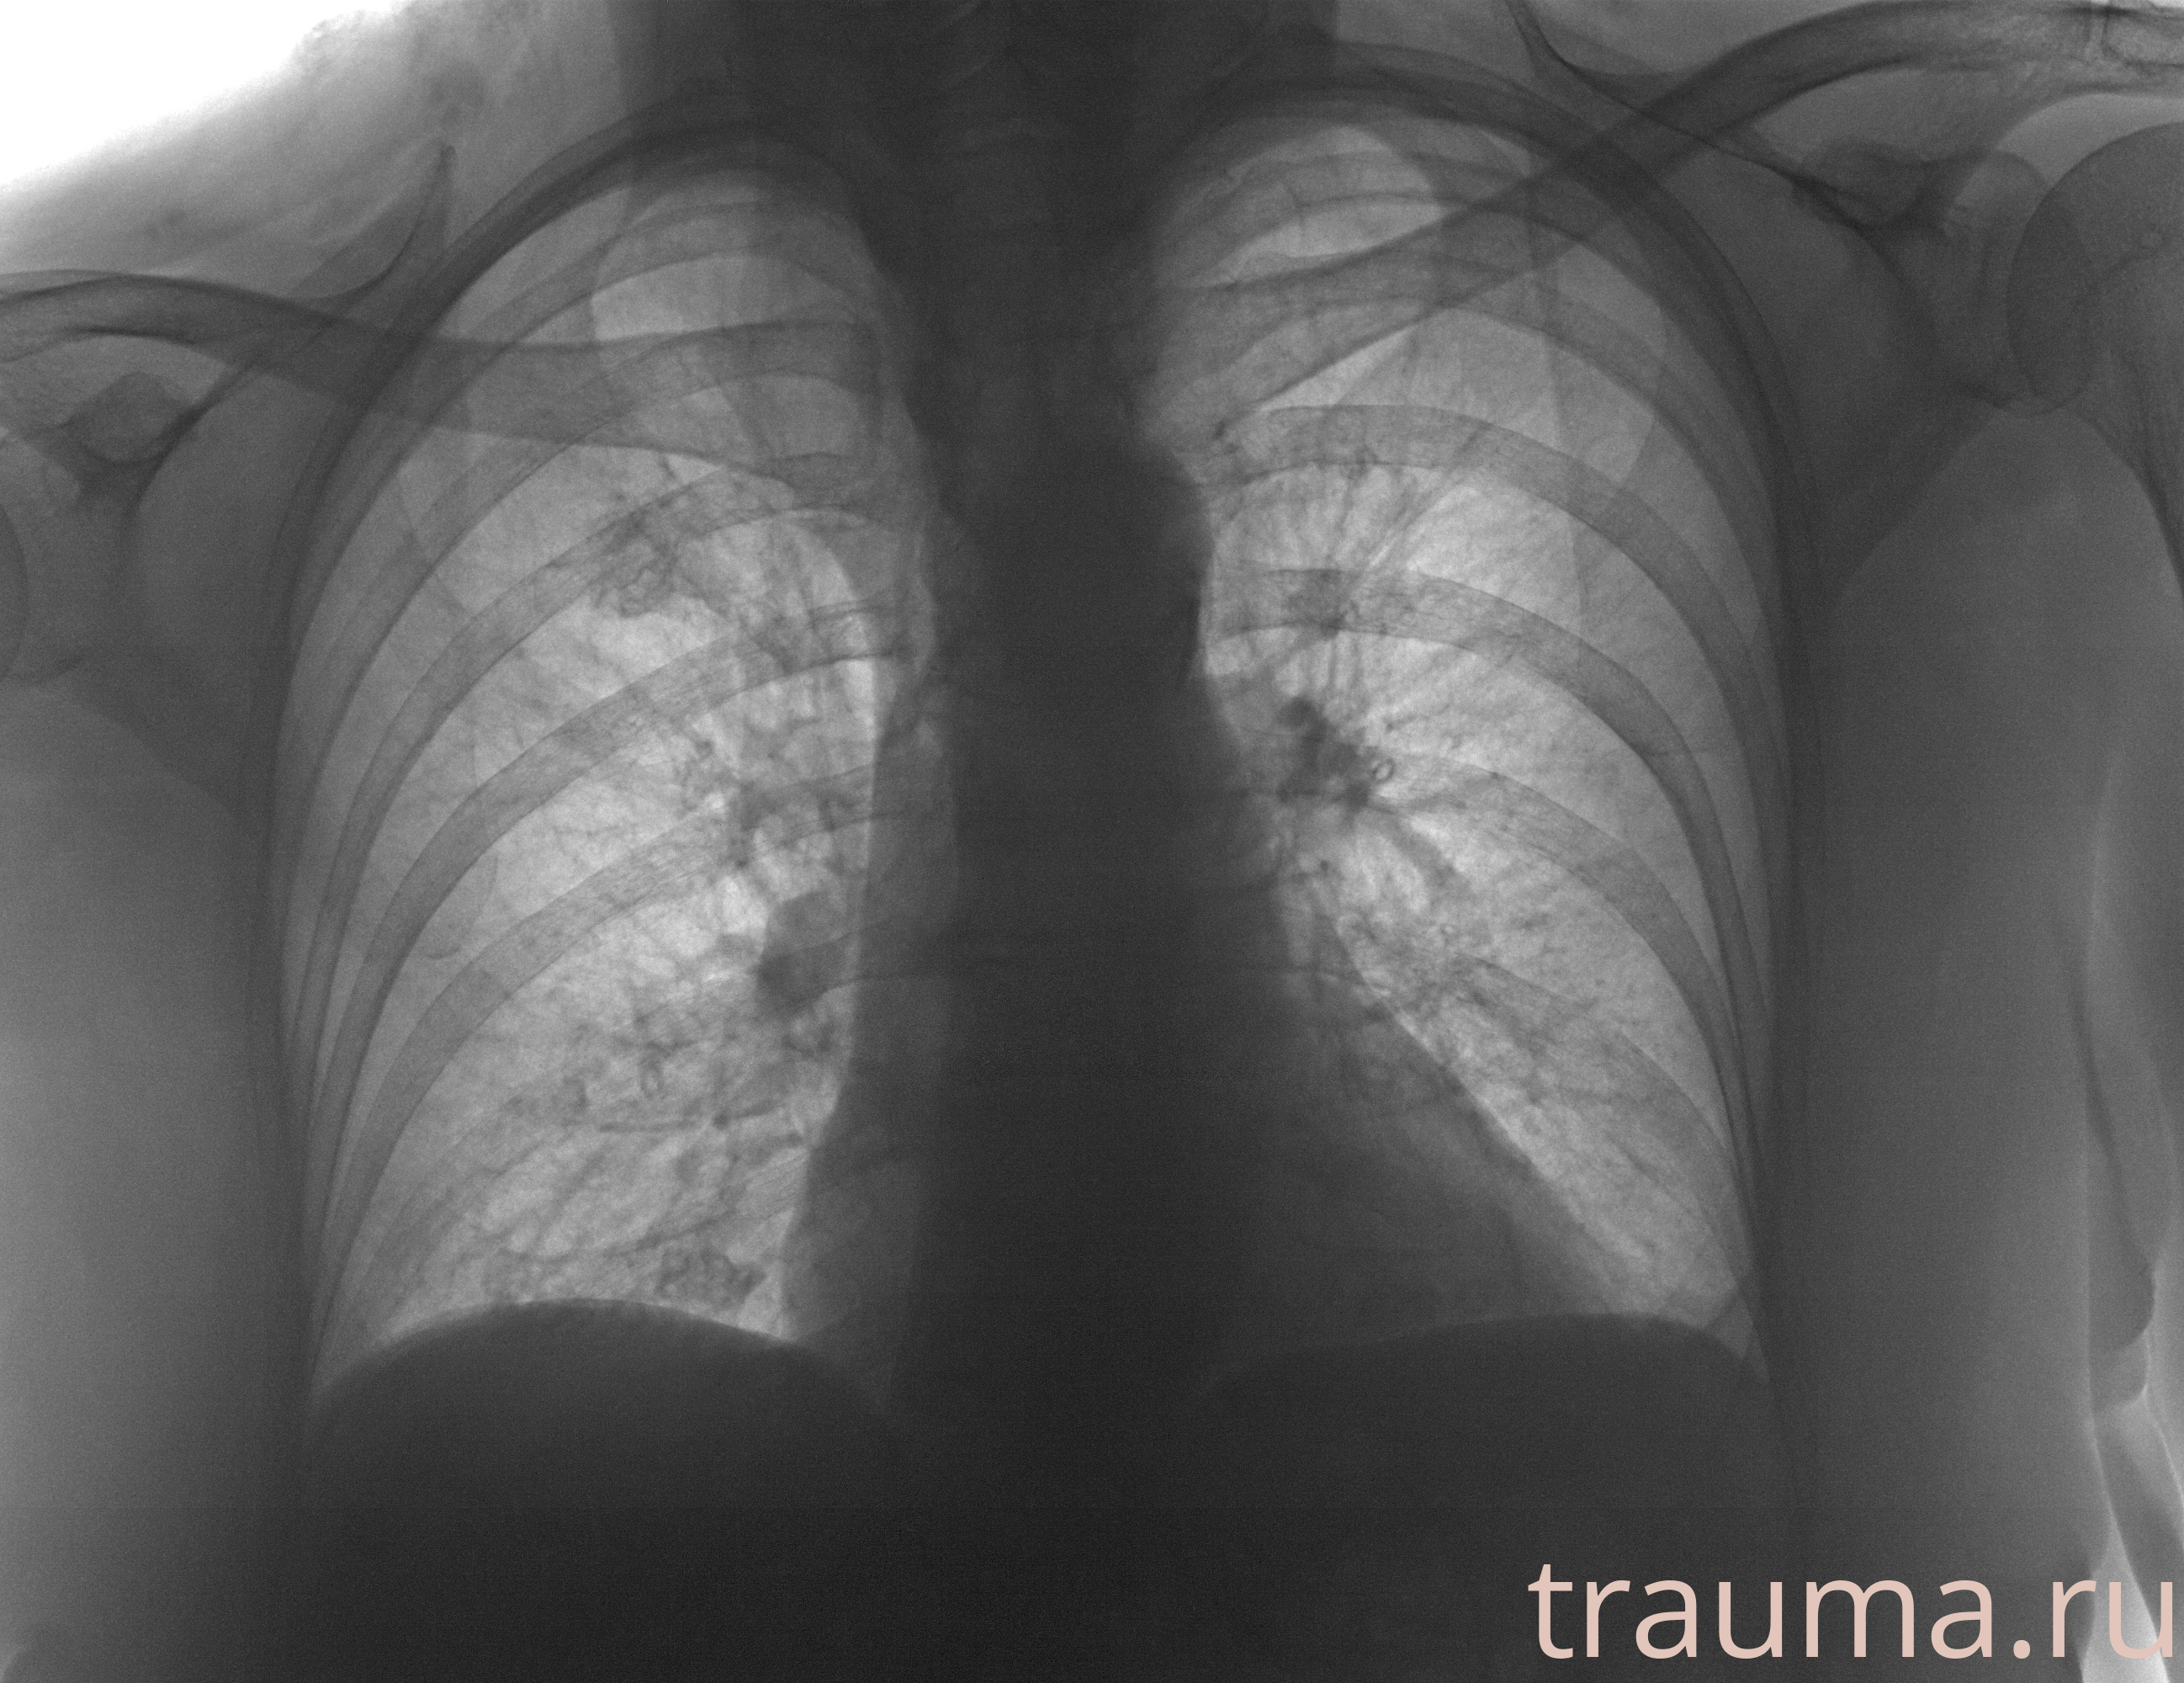

Рентгенограммы

Рентген на дому: по вашему адресу приезжает врач-рентгенолог, травматолог-ортопед с мобильным рентгеновским аппаратом, проводит диагностику травмы или заболевания, делает необходимые рентгенограммы, дает рекомендации по дальнейшему лечению. Получить качественные снимки в домашних условиях возможно благодаря уникальной методике, разработанной МосРентген Центром для института  Склифосовского

при переломе шейки бедра и пневмонии от компании МосРентген Центр - партнера Института имени Склифосовского